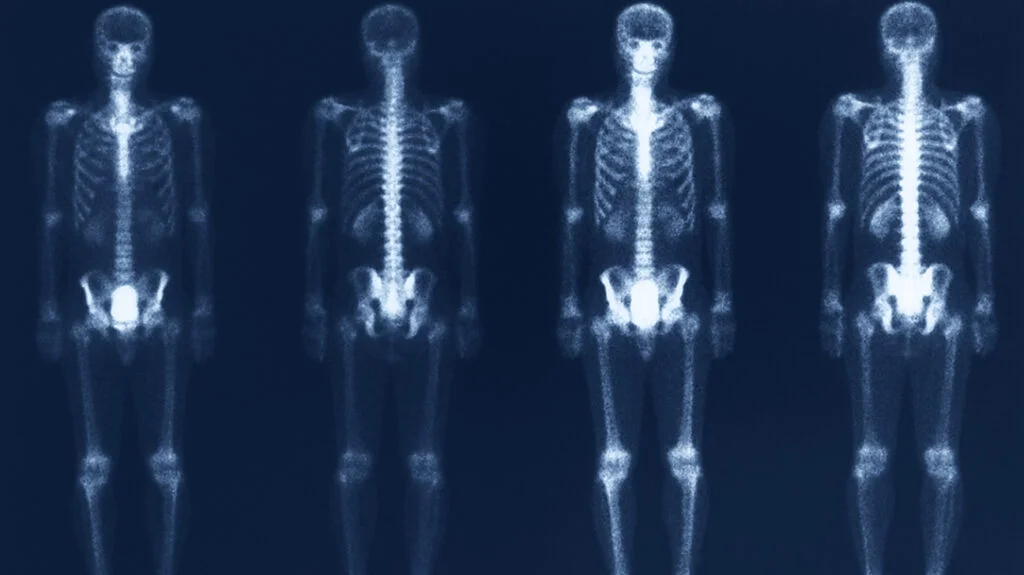

Bone Density Scan, also referred to as DEXA Scan, is considered to be one of the optimal ways to diagnose osteoporosis. This scan is used to measure the minerals of bone by using a low-dose X-ray. This method is considered to be a painless and non-invasive test, which is usually performed on the hip and spine.

A Bone density scan helps to detect early bone loss, which further helps to diagnose whether someone has osteoporosis or not. As health conditions such as osteoporosis do not show any symptoms, which makes people unaware of it, it may impact their bones by creating a hole in them and weakening them. So, if someone has such a serious concern, then the bone density scan helps to get a clear picture of their condition.